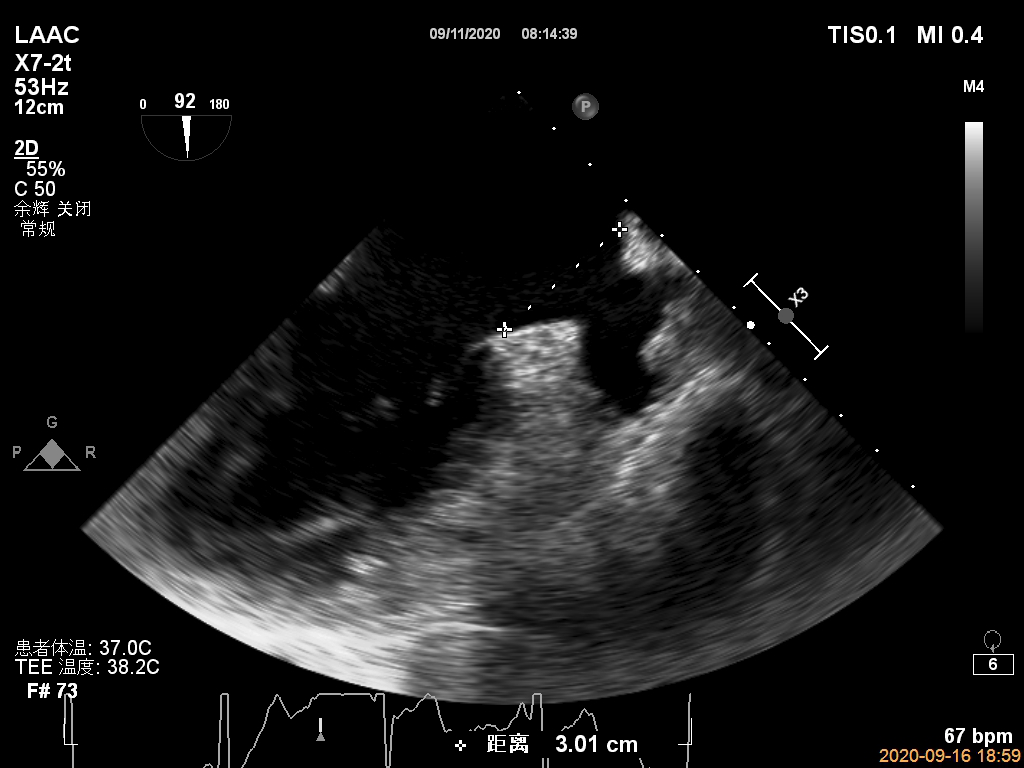

图2:2020年9月TEE检测未见心耳血栓

图5:TEE测量固定盘着陆区尺寸20 mm,覆盖盘外口尺寸30 mm(盖式封堵伞测量)